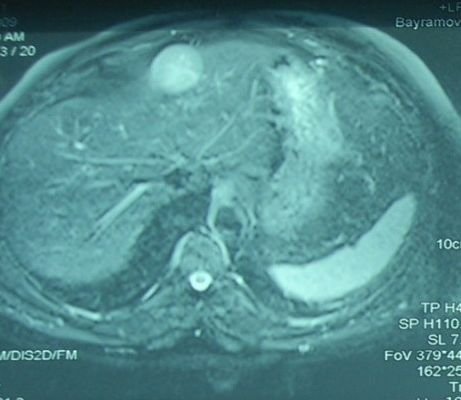

Əməliyyatdaxili ultrasəs müayinəsi 5MHz T tipli linear və ya əyri transdüser ilə aparılır (şək.1)

Transabdominal müayinələrdən fərqli olaraq US gel yerinə normal fizioloji məhluldan istifadə olunur. Ilk olaraq qaraciyər anatomik quruluşu müəyyən edilir (seqmentlər, damarların anatomiyası, öd yollarının variantları və s.) (şək.2)

Damarların anatomiyası və qan axının ölçülməsi rəngli Doppler müayinəsi ilə aparılır (şək.3).